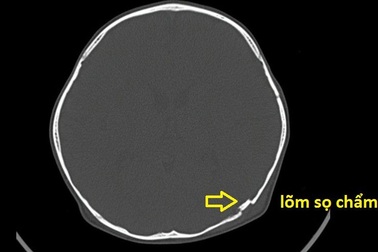

Cậu bé 2 tuổi bị lõm hộp sọ vì tai nạn nguy hiểm thường gặpNhập viện trong tình trạng đau đầu, nôn ói, các bác sĩ phát hiện bệnh nhi bị lõm hộp sọ vùng chẩm trái. Tai nạn nguy hiểm từ cú té xe đạp khiến cậu bé phải phẫu thuật để nâng bản lõm sọ.